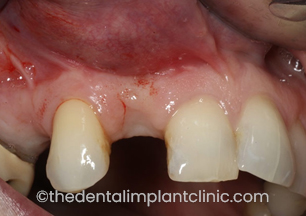

Jane was knocked over by a car aged 11 and her two front teeth experienced a severe trauma and subsequently died. For almost three decades, Jane had received extensive dental work including crowns and bridges. These continued to fail and she also experienced a number of abscesses as a result of the problems with her two front teeth.

‘I was referred by my dentist to The Dental Implant Clinic as he felt that implants were the only solution to my ongoing problems with my two front teeth. For my initial consultation, I was very impressed and the before and after pictures of previous patient cases really convinced me to take the dental implant route.’

The treatment

Because of the huge amount of dental work Jane had previously received, she had become quite concerned about the implant treatment. The Dental Implant Clinic explained that all of the major work could be carried out under sedation and also suggested that she have a friend accompany her to offer support prior to being sedated. Following the initial consultation, the two teeth were carefully removed and replaced by two implants. During the period that the implants were healing, a denture was fitted.